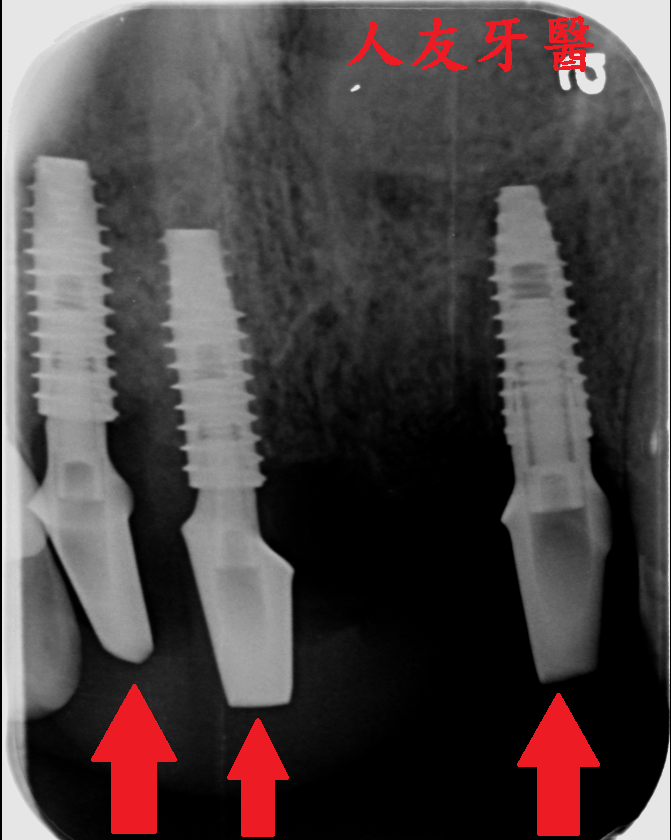

拔完牙後一個月,看傷口癒合情況,因兩顆門牙缺牙太久,齒槽骨流失比較多,醫師建議補骨跟植牙同時進行,植入三根牙根,位置分別在於右邊側門牙一顆,右邊正門牙和左邊側門牙。

再用左邊側門牙牙套搭橋到右邊正門牙牙套(三顆相連),右邊側門牙獨立做牙套。使門面變好看,說話也不會漏風。